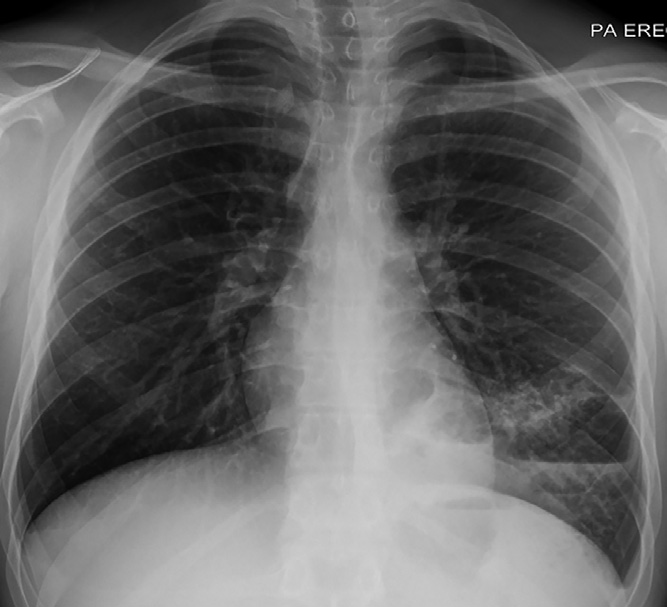

實驗室檢查顯示白細(xì)胞計數(shù)13.6×109/L↑(中性粒細(xì)胞79%;淋巴細(xì)胞12%),C反應(yīng)蛋白96 mg/L↑。胸部X線檢查顯示左肺下葉實變伴氣液平面,考慮與空洞性肺炎相關(guān)(圖1)。增強CT顯示左肺下葉病變,有空氣支氣管征和含氣液平面的空洞及囊狀氣腔。(圖2A–2 C)。人類免疫缺陷病毒抗體檢測、抗中性粒細(xì)胞胞漿抗體、尿肺炎球菌和軍團菌抗原檢測均為陰性,且多組血培養(yǎng)結(jié)果顯示無菌?;颊呦惹拔催M行IgG及亞類缺陷檢測。

圖1 胸部X線顯示左肺下葉實變伴氣液平面,未發(fā)現(xiàn)明確腫塊。該結(jié)果與空洞性肺炎相關(guān)。